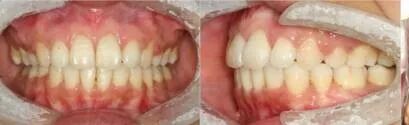

张女士,29岁,牙齿露龈笑

在天使进行陶瓷自锁托槽矫治后

牙齿变得整齐,脸型也变得和谐了,

笑起来也更加自然漂亮了~